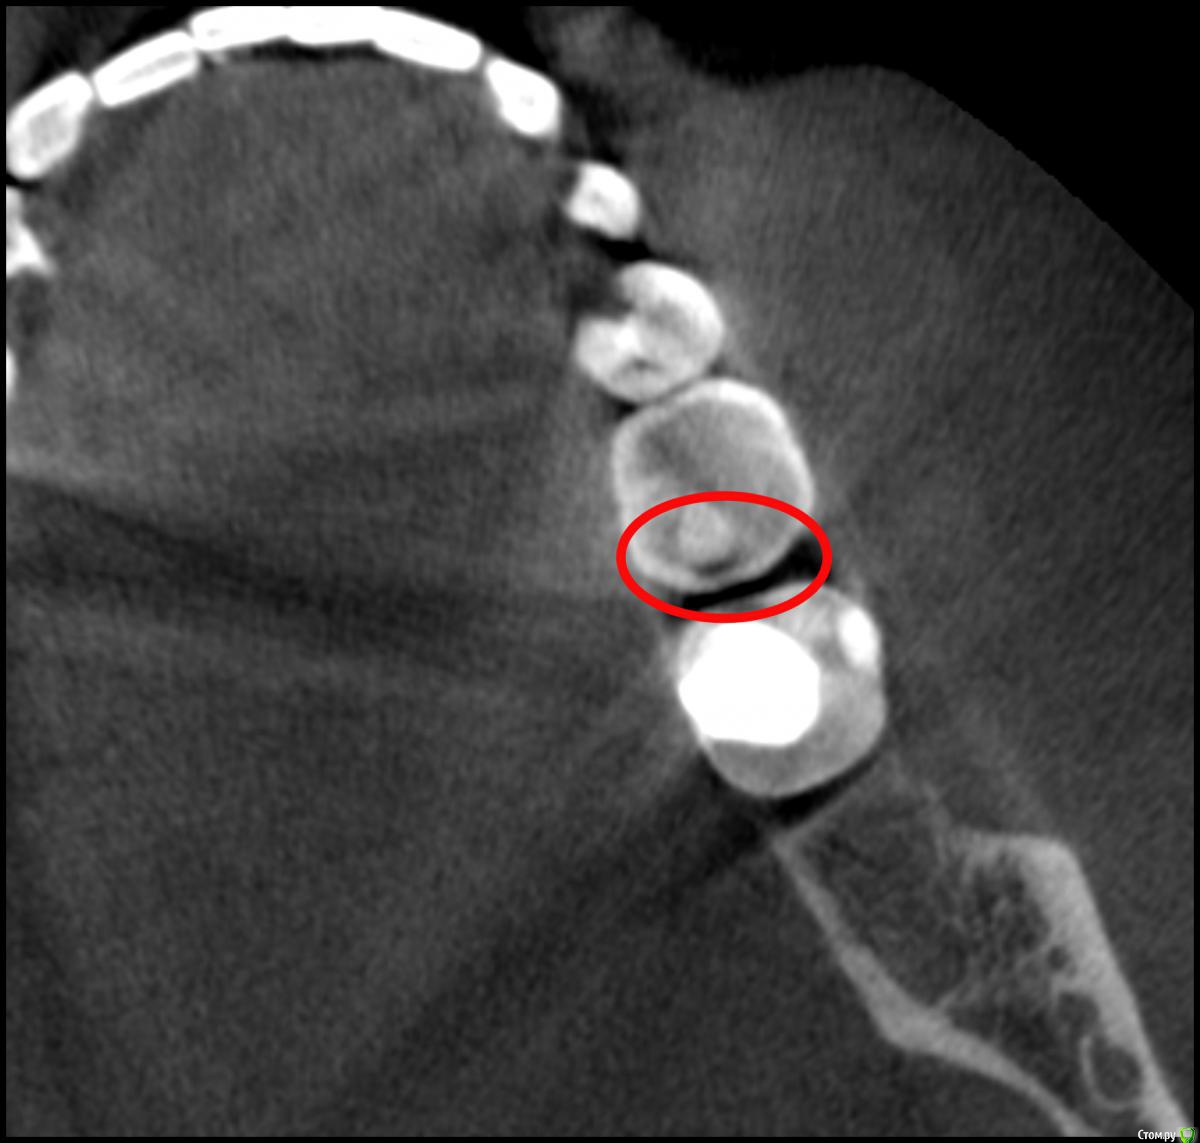

Nick-ev Опубликовано 6 апреля, 2019 Поделиться Опубликовано 6 апреля, 2019 2 месяца назад запломбировали зуб, не болел вообще, но стоматолог увидел что то на нем.Недавно делал КТ и увидел затенение под пломбой.Пожалуйста посмотрите, что это на снимке. Ссылка на комментарий

Nick-ev Опубликовано 8 апреля, 2019 Автор Поделиться Опубликовано 8 апреля, 2019 По кт кариес под пломбой диагностировать практически невозможно, его обычно делают в других целях а что это за темное пятно под пломбой? Ссылка на комментарий

___49___ Опубликовано 8 апреля, 2019 Поделиться Опубликовано 8 апреля, 2019 а что это за темное пятно под пломбой?Возможно кариес, возможно рентген не контрастный цемент или др материал .. Такого рода клинические случаи получают диагноз по совокупности данных объективных исследований, жалоб и клинических проявлений - что можно сделать только в кресле у врача. Коллега права - под пломбой диагноз по КТ весьма затруднителен, а вот зуб сверху над тем что вы указали с кариесом и диагноз тут очевиден , так как пломбы нет и рентген не контрастное вещество в него до нас не закладывали . Ссылка на комментарий